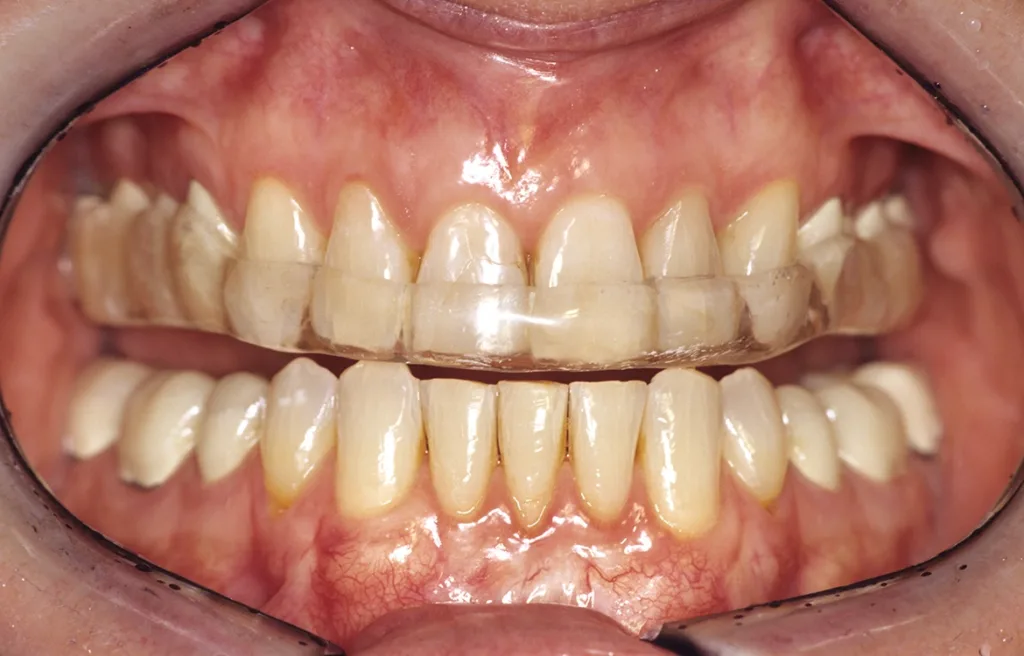

- Anfertigung einer Relaxierungsschiene im OK (bei Deck- oder Tiefbiss im UK) zur funktionellen Dekompensation mit frontalem Aufbiss und temporärer Entlastung im Molarenbereich durch vertikale Freistellung von 1 mm (GOZ 7000 ff.) (Abb. 5 bis 7).

Ziel ist die Dekompensation gewohnheitsbedingter Fehlfunktionen zur Entlastung, Revaskularisierung und Mineralisation des Alveolarknochens vor Implantation. Nach Durchführung der genannten Maßnahmen erfolgt bereits nach einer Tragezeit von vier bis sechs Wochen eine Entlastung von habituellen Gebrauchsmustern. Aus Hygiene- und Stabilitätsgründen werden die Schienen als Streuschienen in einer Stärke von ca. 1,5 mm gefertigt. Sie reichen jeweils bis zum Sechsjahrmolaren (Abb. 8).